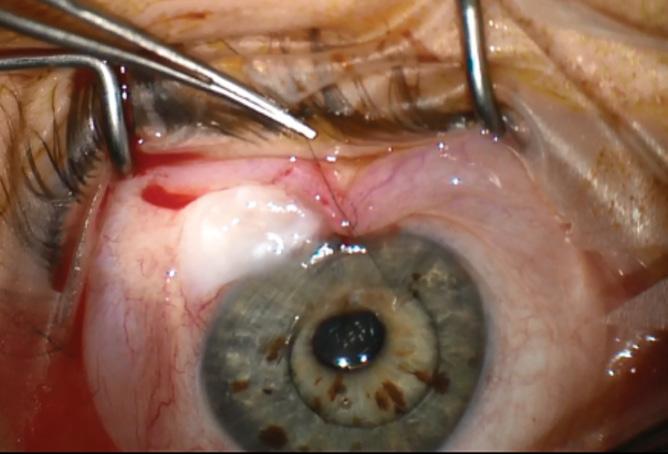

Post-paediatric cataract surgery Glaucoma: A: 3.5 years old child with cataract surgery done in infancy. Glaucoma with enlarged corneal diameter and a dislocated IOL are seen. One previous Ahmed glaucoma valve (AGV) in supero-temporal quadrant has failed to control IOP adequately; B: A second AGV plate is sutured in the infero-temporal quadrant. A closed chamber vertical translocation of haptics to glued IOL is then done sitting temporally, taking advantage of smaller vertical diameter of cornea; C: Adequate length of the externalised haptics of the IOL is seen; D: Haptics are tucked in. A well-centred IOL is seen. The AGV tube tip is positioned posterior to the iris in front of the IOL. Adequate vitrectomy is performed during IOL translocation as well as after inserting the tube tip